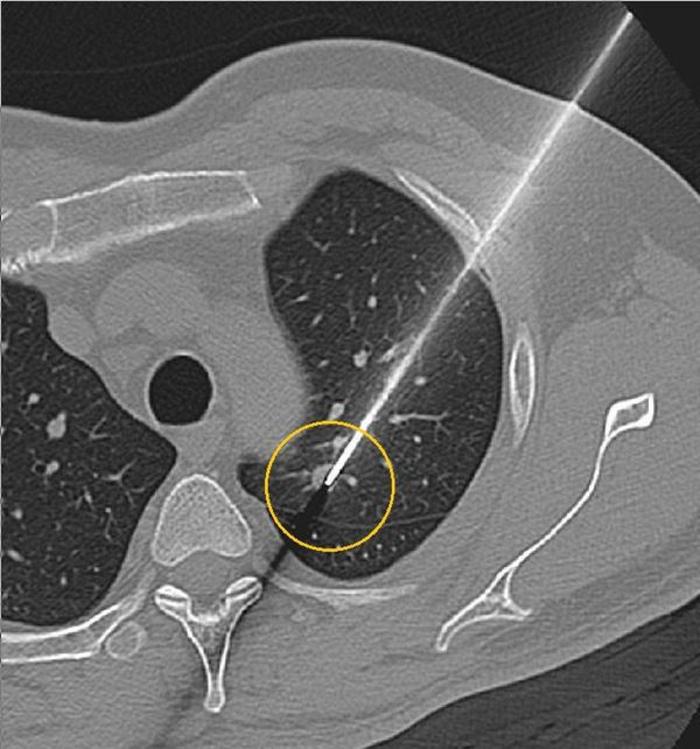

随着大家了解的医学知识越多,越来越多的朋友认识到:疑似肺癌若想确诊,最重要的手段就是穿刺活检,只有病理学才是诊断的金标准。那是不是所有的肺结节都能做穿刺活检,做了活检又是否一定能检出肺癌?

所有的医学操作都是有适应症和禁忌症的。关键在于是否有穿刺禁忌,不然都能做穿刺活检。目前我们认为的绝对禁忌症就是不可纠正的凝血功能障碍,比如一些血液病的病人。至于存在严重肺动脉高压、感染性病变、肺气肿等等疾病的患者,则需要综合考虑,也取决于医生的穿刺技术。

但有一点需要跟大家说明的,目前从研究报道来看,胸部穿刺活检对恶性疾病诊断准确性为64%~97%,对良性疾病诊断局限性大,准确性约10%~ 50%。病灶大小和位置、操作者经验、引导方式选择、细胞学评估均影响诊断准确性。